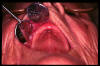

CM Ulcera traumática